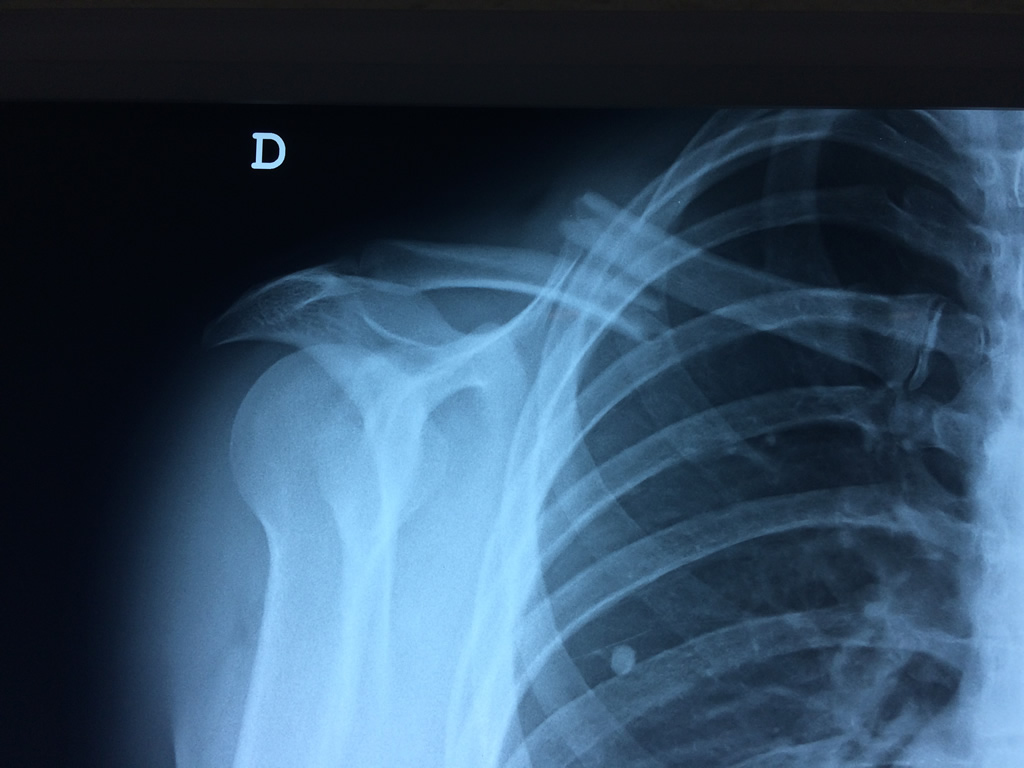

Cirugias en El Salvador - Clavícula

La clavícula es un hueso largo, con forma de "S" itálica, situado en la parte anterosuperior del tórax. Junto con la escápula forman la cintura escapular. Se puede palpar por toda su longitud y se extiende del esternón al acromion de la escápula, siguiendo una dirección oblicua lateral y posterior.

Se considera el único medio de unión entre el miembro superior y el tórax. A pesar de su aspecto, similar al de un hueso largo, posee una estructura semejante a la de un hueso plano, ya que carece de epífisis y de diáfisis, lo que la harían entrar dentro de la clasificación de hueso largo. Carece de un canal medular propiamente dicho.